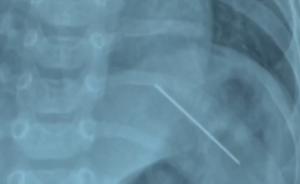

近日,江苏常州。一名约4月大的婴儿常哭闹发烧,父母带其到医院检查发现,孩子腹腔内有一根针。同时家人发现孩子的新衣上也扎有两根针。经手术,缝衣针已从婴儿体内取出。